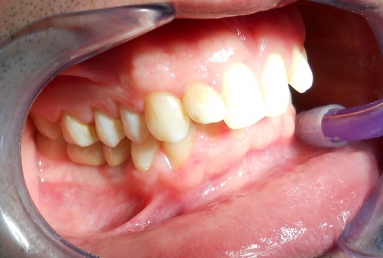

Initial situation: two missing teeth, second lower premolar and first lower molar. two dental implant are integrating in the mandibular bone for 4 months, then, gingival healing caps are applied for 3 weeks. an impression is taken for the dental lab in order to manufacture 2 porcelain fused to metal crowns. they will be screwed directly in the implant body.